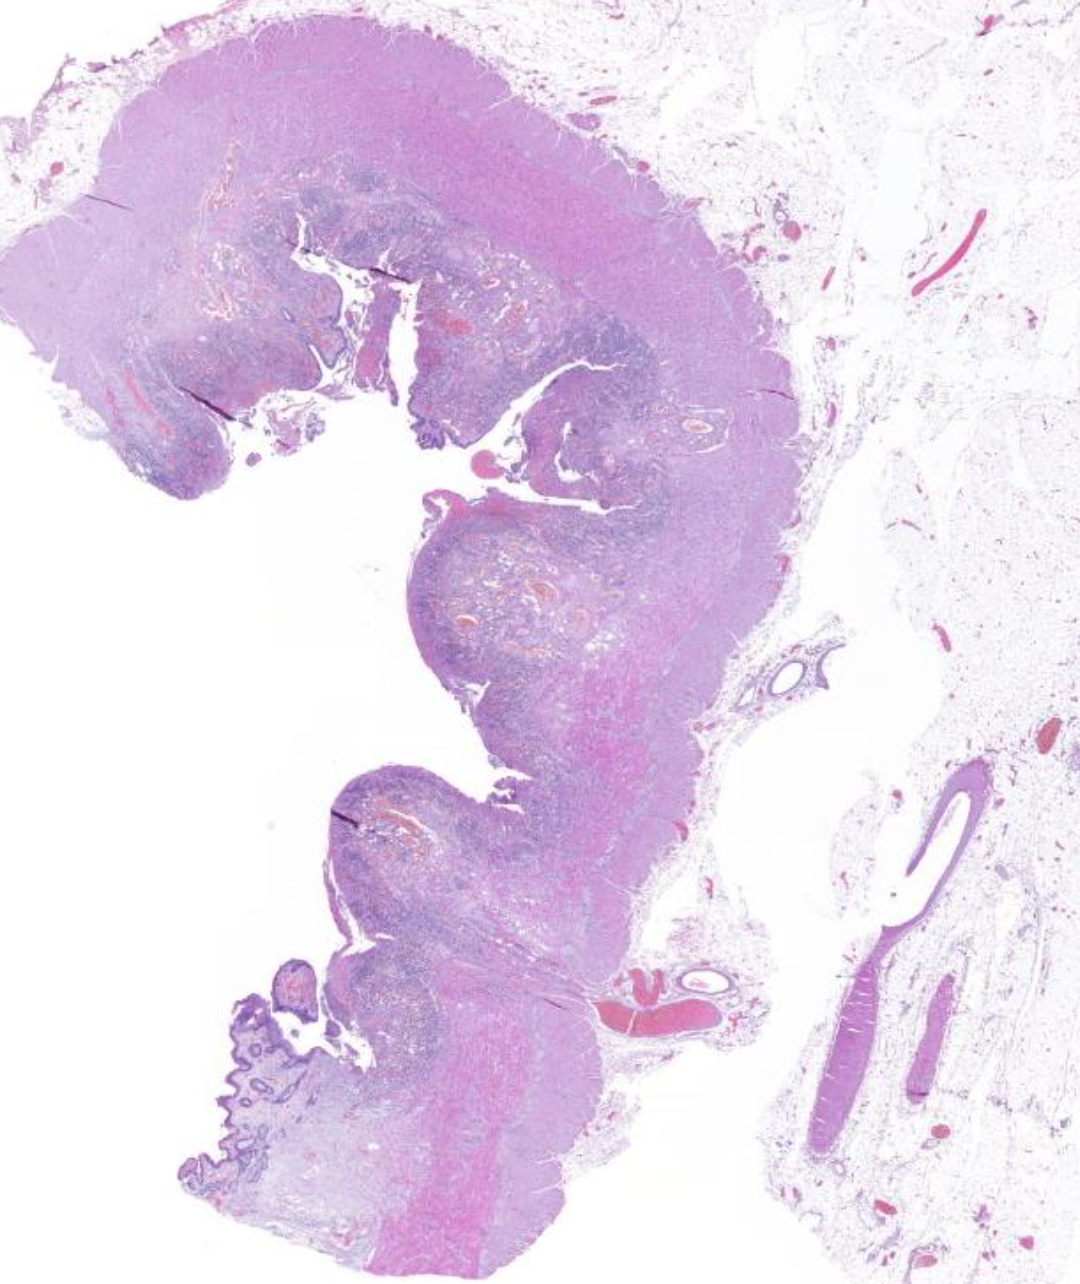

Diagnose?

Adenokarzinom des gastroösophagealen Übergangs = Barettkarzinom

Viel häufiger als Plattenepithel-CA, wird immer irregulärer je höhergradig und tieferreichender der Tumor ist, Dysplasie ist Vorstufe und Notwendigkeit zur Therapie